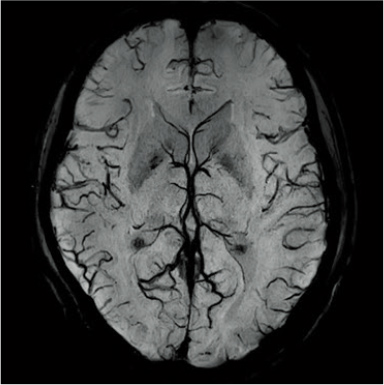

RADAR’ın TOF MRA ve GrE T2*WI’deki etkileri

RADAR, yüksek hassasiyetli sinyal düzeltme teknolojisi kullanılarak GrE sekanslarına uygulanmıştır. Bu, rutin baş incelemelerinde gerekli tüm sekanslar için RADAR’ın kombine kullanımını mümkün kılmıştır.